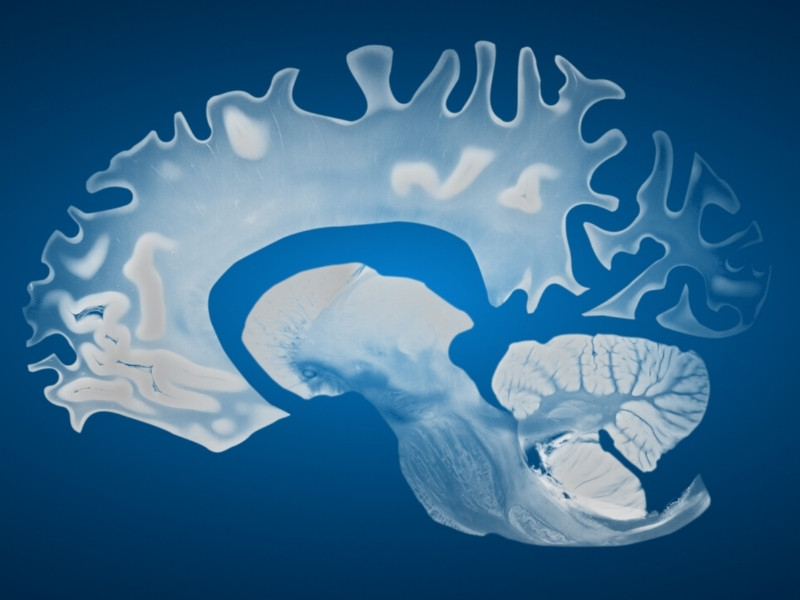

Thoái hóa thần kinh là thuật ngữ mô tả quá trình tổn thương và chết đi của các tế bào thần kinh trong hệ thần kinh trung ương hoặc ngoại biên. Khi quá trình này xảy ra, chức năng thần kinh dần bị suy giảm, dẫn đến các biểu hiện lâm sàng nghiêm trọng như mất trí nhớ, rối loạn vận động hoặc thậm chí tử vong.

Không giống với các bệnh cấp tính chỉ ảnh hưởng tạm thời, thoái hóa thần kinh thường tiến triển âm thầm, mạn tính và không thể phục hồi hoàn toàn. Những bệnh lý này thường khởi phát ở tuổi trung niên hoặc cao tuổi, nhưng một số thể bệnh có thể biểu hiện sớm hơn.

- Chụp cộng hưởng từ (MRI) để phát hiện teo não, tổn thương demyelination.